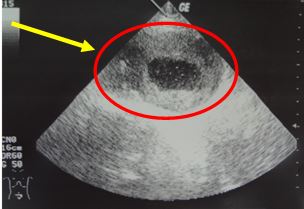

+ Siêu âm ổ bụng:

Vùng hạ vị có khối hỗn hợp âm kích thước 12 x 6,3cm.

Kết luận siêu âm: Nang thận trái, khối u vùng hạ vị theo dõi u mạc treo

Hình 1. Hình ảnh siêu âm ổ bụng: Khối u vùng hạ vị có hoại tử bên trong